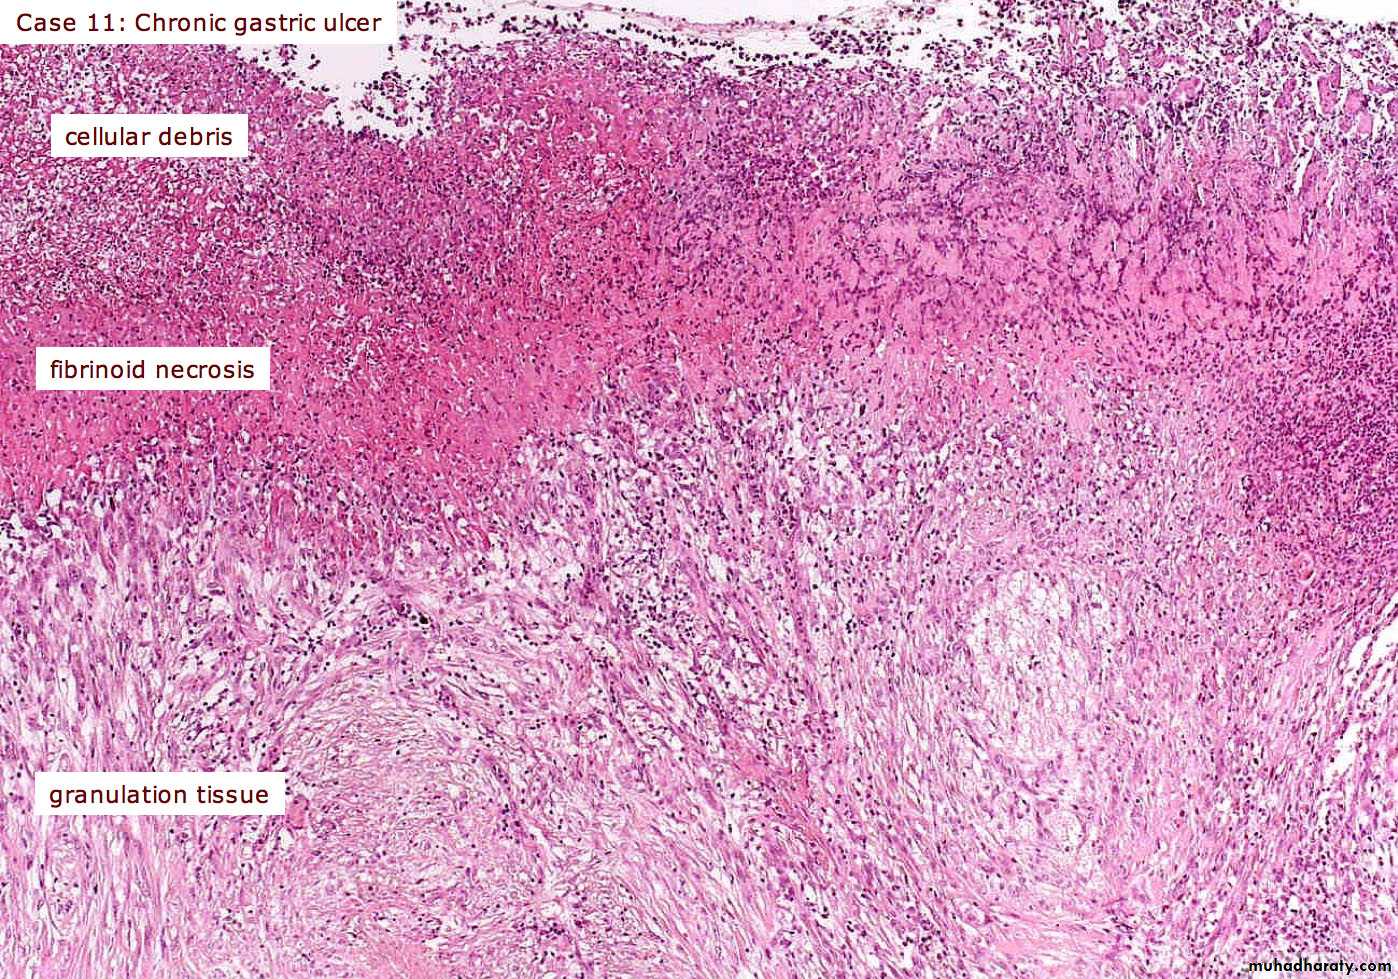

Granulation tissue

It is part of the healing process of wounds and is consist of newly formed blood vessels (angiogenesis) and recruitment of fibroblast to the sight of injury and collagen fibers deposition that lead to make a mesh , it start from bottom and sides of the wound